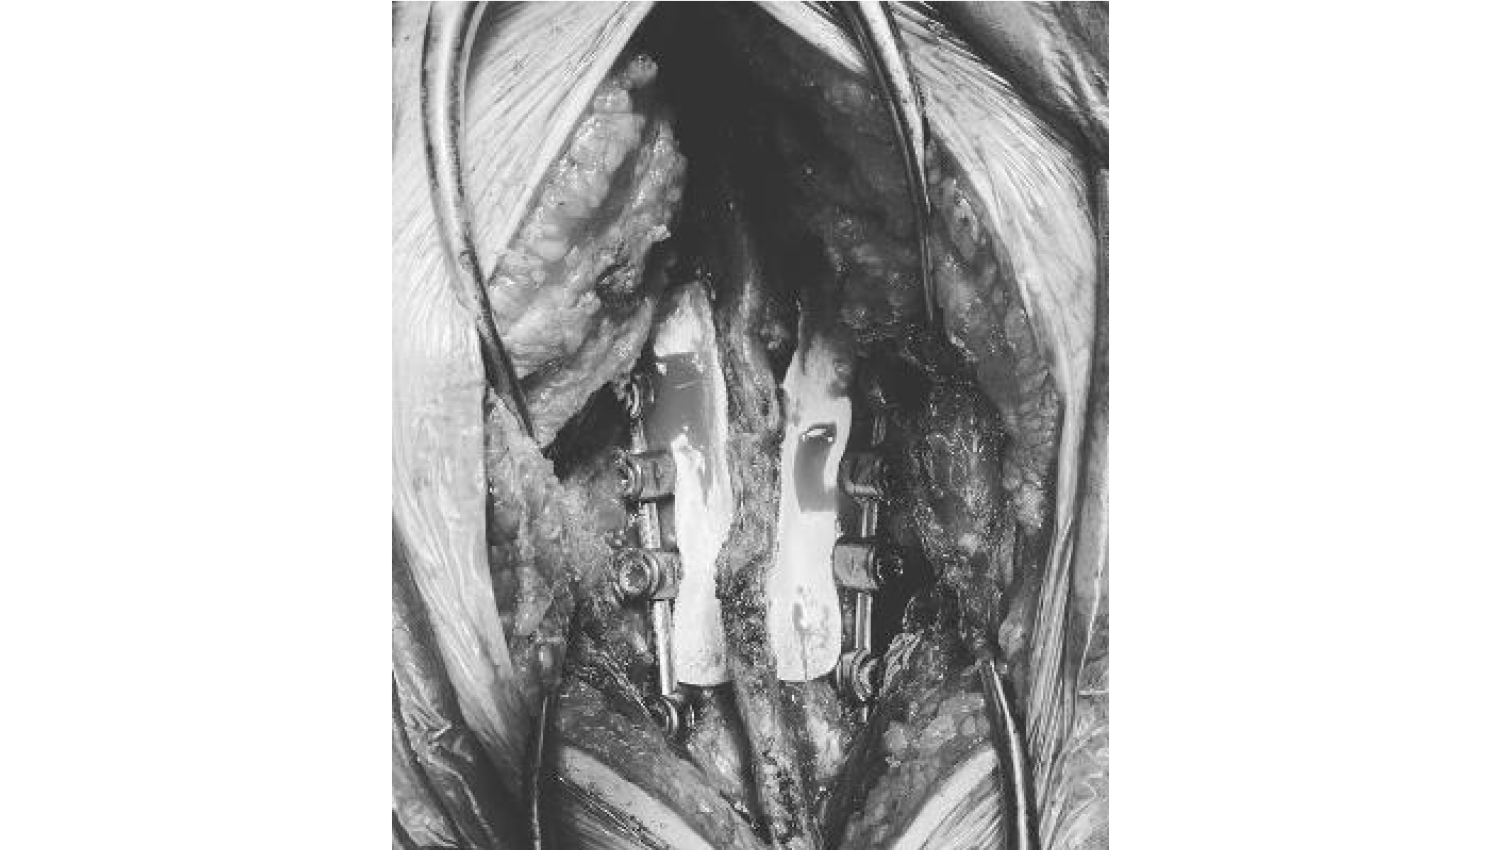

4.The Powerbone Flexible Graft is cut to the required dimensions for implantation and wetted with the patient's blood and implantation is performed. After mixing the Powerbone Bone Cement product, it was implanted in the relevant area.